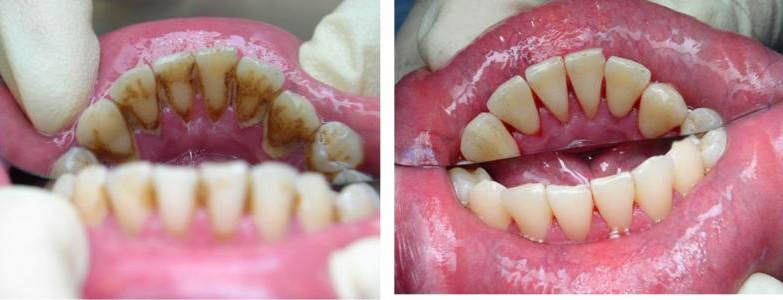

Зубной камень: фото до и после

Зубной камень — это затвердевший налет, который не был удален во время домашних процедур по уходу за полостью рта. Кроме эстетических проблем эти отложения способны доставить массу других неприятностей: они провоцируют различные стоматологические заболевания (кариес, гингивит, пародонтит) и в дальнейшем могут стать причиной потери зубов.